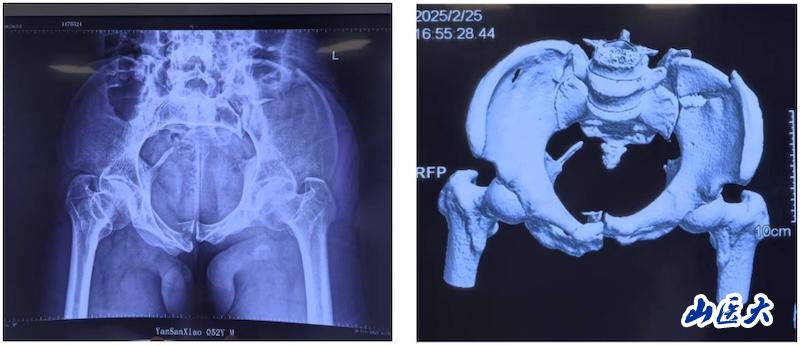

術前 該患者在駕駛三輪車時發生車禍,導致骨盆骨折,經過當地醫院對癥治療后轉入我校第二醫院急診科。由于血色素持續下降,血管外科首先進行了血管介入栓塞處理,隨后轉入骨科創傷病區,由孫海鈺團隊接續治療。經過詳細檢查和評估,孫海鈺主任、賀冬冬副主任醫師、王歡副主任醫師為患者制定了運用UCRT解鎖復位技術,結合天璣機器人及O-arm術中影像系統為其實施骨盆閉合復位的手術治療方案。3月6日,孫海鈺團隊在骨科老一輩專家尹蕓生主任的指導及麻醉師、技師、器械護士和巡回護士的通力協助下,成功運用微創新技術為患者實施了手術。

術中 據孫海鈺介紹,骨盆髖臼骨折是一種嚴重的創傷,傳統開放復位內固定術創傷大、恢復慢,而閉合復位則具有微創、出血少、恢復快等優點。隨著醫療技術的不斷進步,UCRT解鎖復位技術結合天璣機器人及O-arm術中影像系統為骨盆骨折治療提供了更加精準、微創的解決方案,該技術代表了當前骨盆骨折治療的前沿方向。